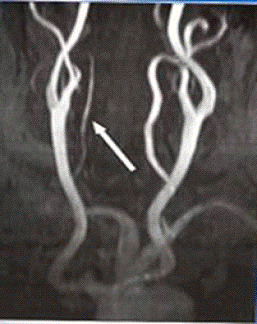

МР-ангиография сосудов головы и шеи позволяет

исключить сочетание костной дисплазии с сосудистой, как то гипоплазия

позвоночных артерий (рис.3), патологические изгибы: кингкинги (рис.4) и

койлинги (рис.5).

Рис. 6 - Гипоплазия позвоночной артерии